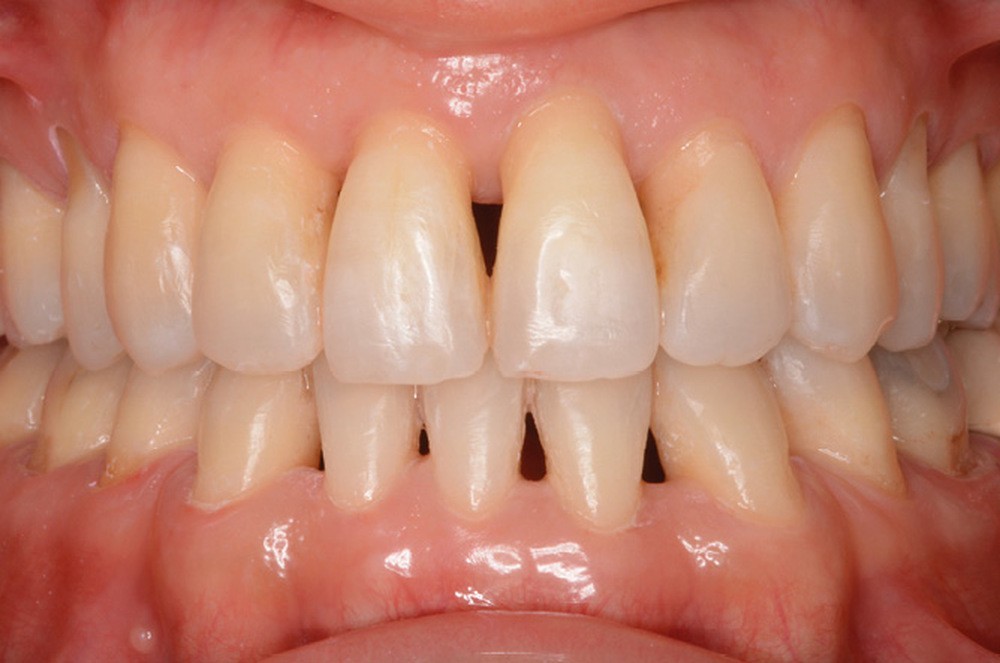

Traitement (fig. 10 à 20)

Une contention collée de 13 à 23 et de 33 à 43 (chaînette en alliage précieux Ortho-flextech), ainsi qu’une gouttière thermoformée maxillaire sont mises en place. Le suivi parodontal est trimestriel.

Notre traitement a permis de répondre à la demande de la patiente [3] en réduisant la compression articulaire dont elle souffrait, atténuant par la même occasion ses symptômes, tout en améliorant nettement son pronostic parodontal et dentaire sur le long terme. Mme J. est très satisfaite du résultat obtenu.